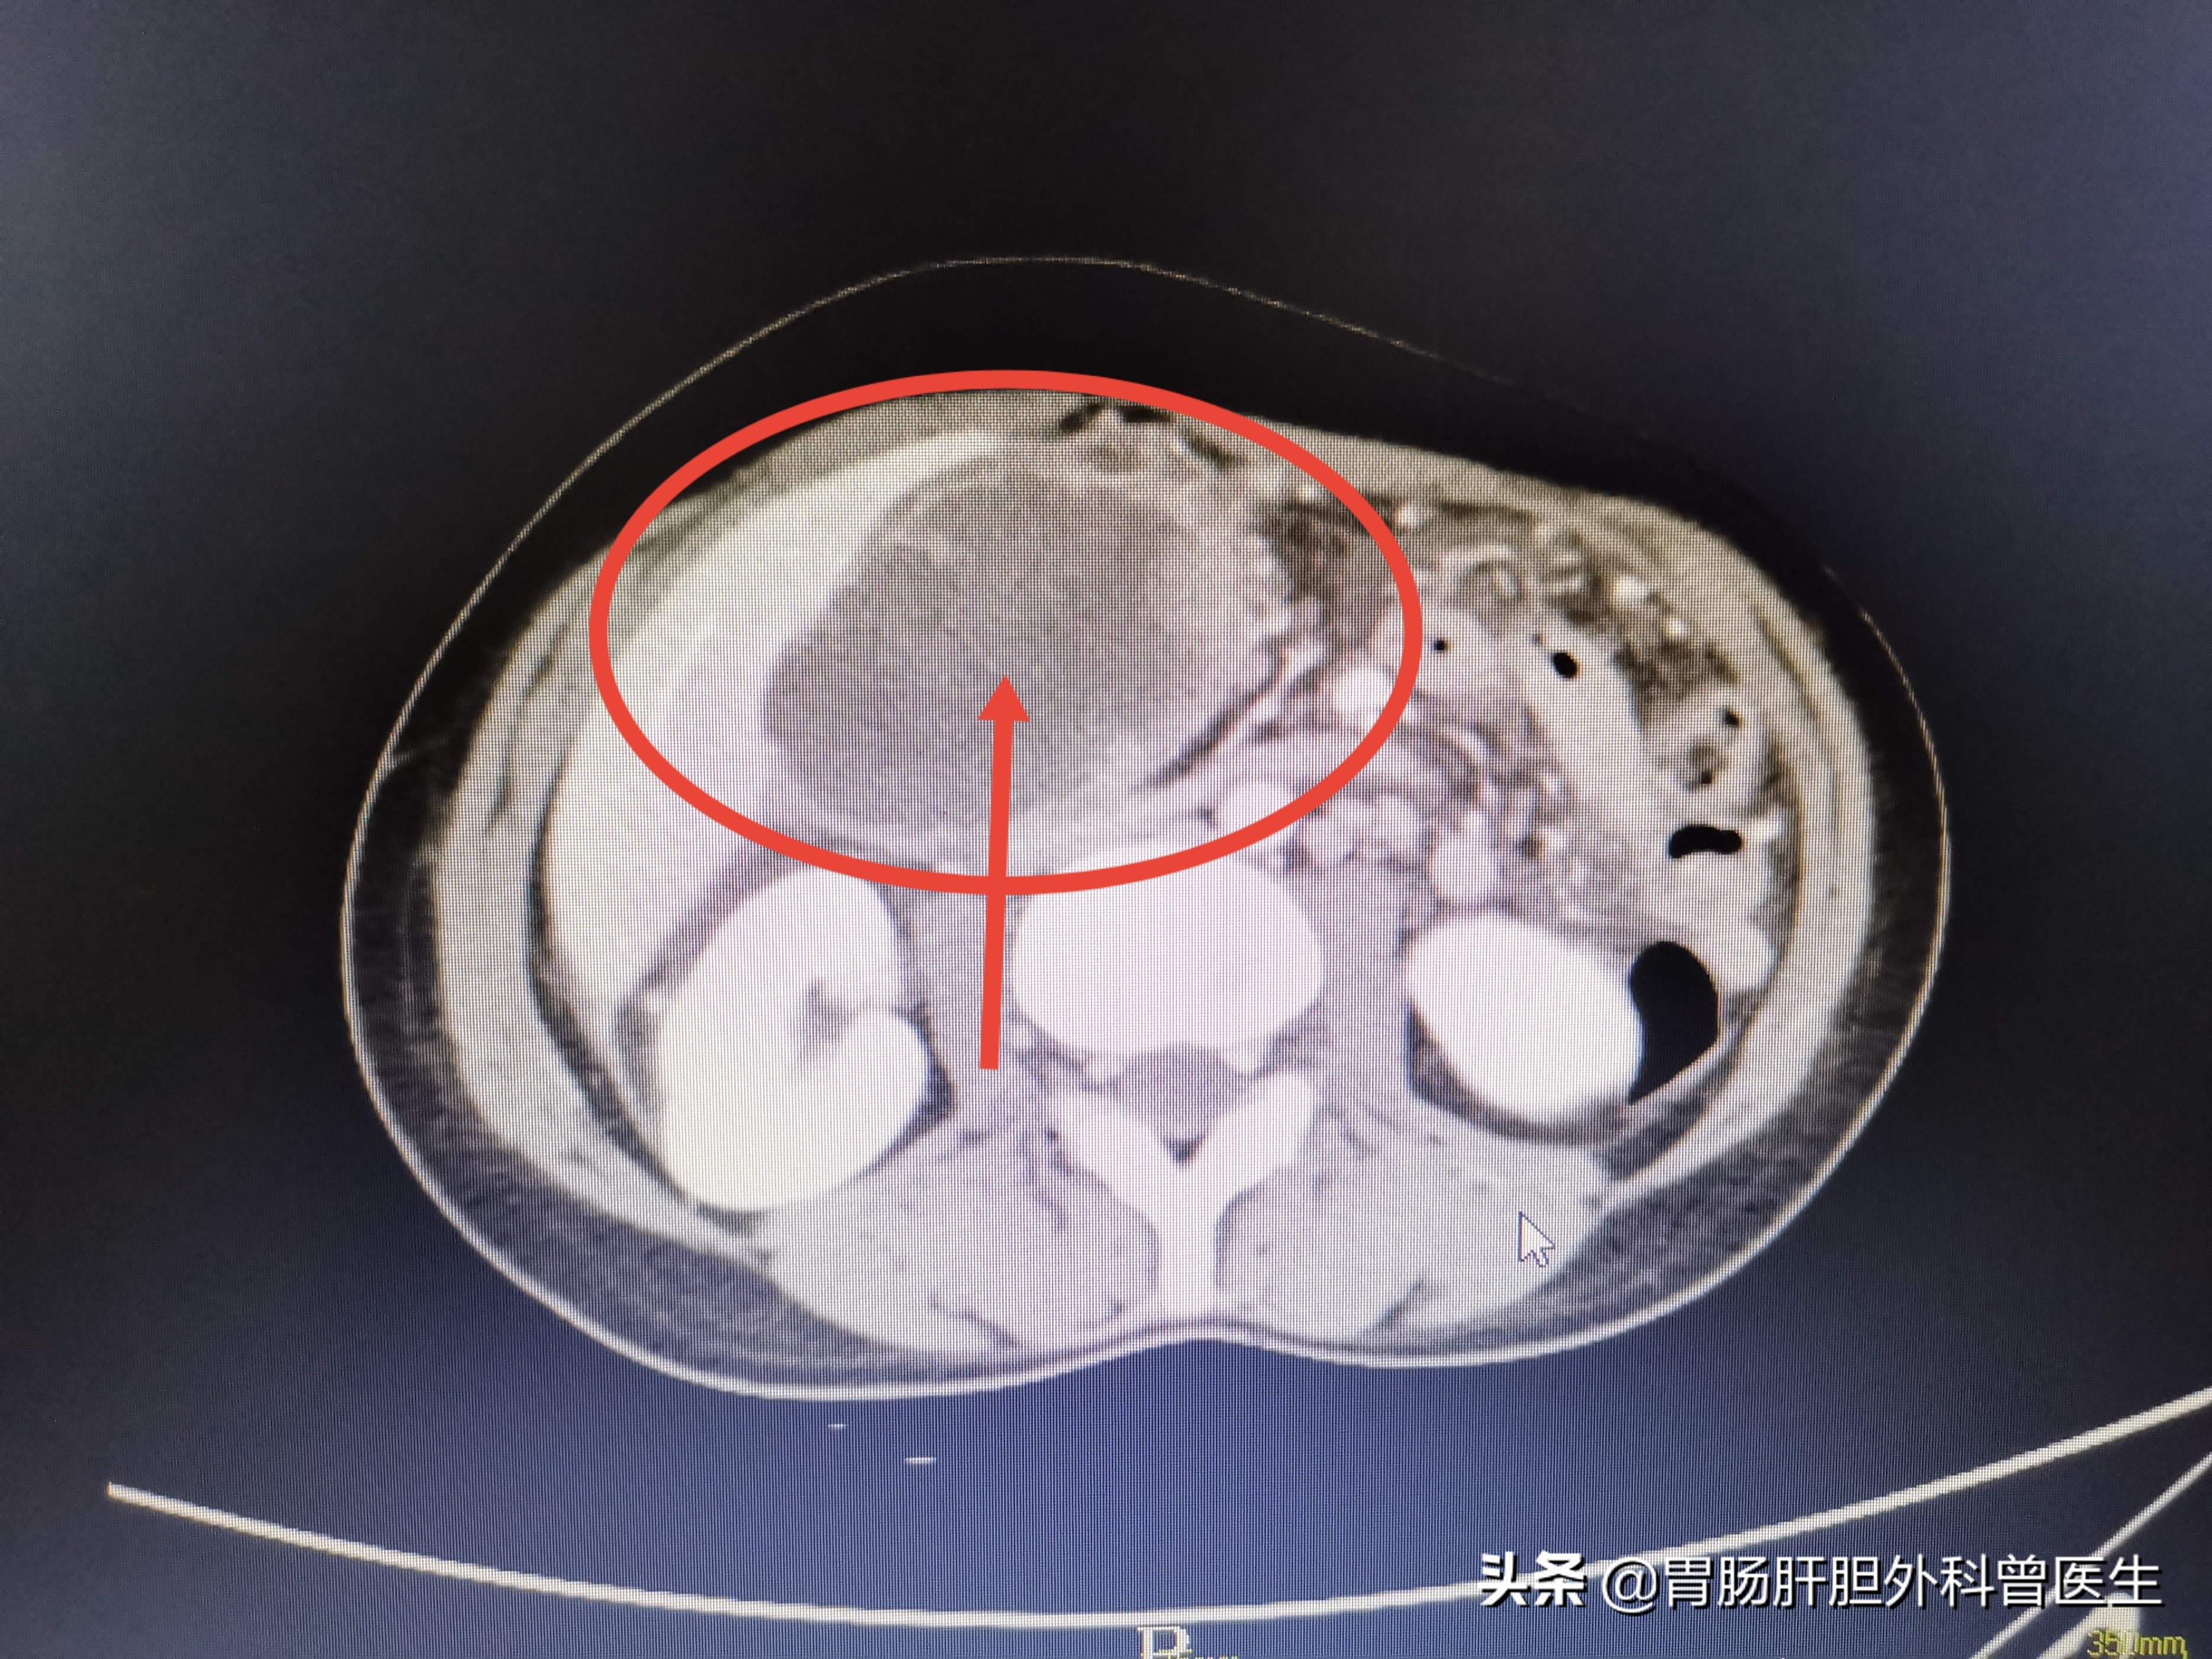

腹部增强CT结果很快出来,当年那颗2厘米的胆囊息肉,现如今已经变成了将近10厘米的巨无霸,并且出现胰头、小网膜、横结肠、腹主动脉、腹腔内淋巴结的多发侵犯和转移!

梁女士癌变肿大的胆囊,比2个肾脏还大